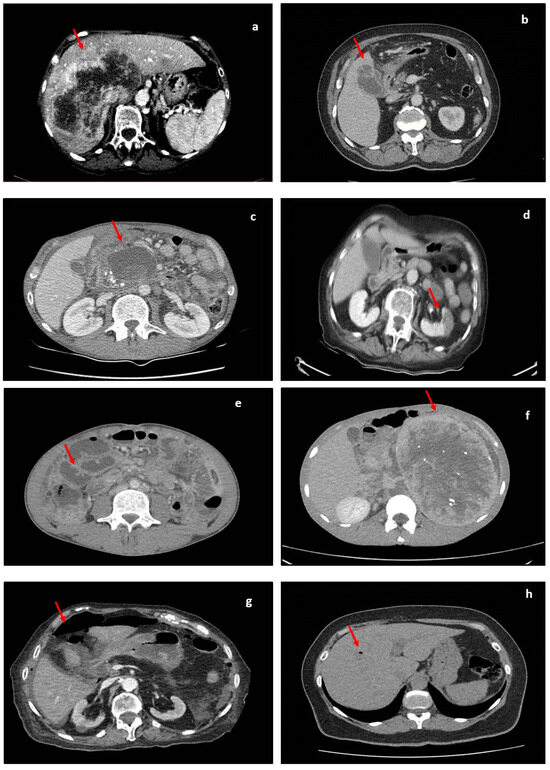

Figure 6.

Different CT findings in abdominopelvic pathologies. Lesions are indicated by red arrows. (a) Image showing a large liver lesion; (b) image showing fat stranding and gallbladder wall discontinuity; (c) image showing a large pancreatic pseudocyst; (d) image showing left-kidney hypoattenuation during the venous phase, which is suggestive of ischemic changes; (e) image showing multiple distended small-bowel loops; (f) image showing a large left-retroperitoneal mass; (g) image showing a pneumoperitoneum; (h) aerobilia; (i) acute appendicitis coronal (fat stranding around the caecum and an inflamed appendix); (j) image showing perisigmoidian fat stranding and air pockets in acute diverticulitis.